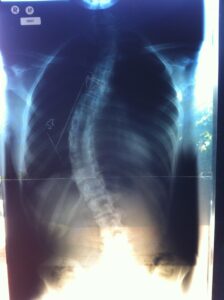

As a result, she noticed that my spine was severely curved. At this point, we had no idea what Scoliosis was, and had never even heard the word.

Unfortunately, like most adults, my Mum and Dad were not aware of the condition and therefore missed the subtle signs during the early stages of my Scoliosis. I was a fit and healthy child and up until that point, and had never complained about my back. Mum took me to our local GP who referred me to an Orthopaedic Surgeon, Mr Griffin. He diagnosed my Scoliosis and decided that we monitor it for 12-18 months. Unfortunately by this stage, my Scoliosis was too severe for bracing and as a result Scoliosis surgery was my only option.

We went along to see another Orthopaedic Surgeon, Mr Robert Dickens who specialized in Scoliosis surgery. He explained that my curve was likely to progress by ten degrees per ten years. The curve would become cosmetically more inappropriate, cause respiratory complications and ultimately would shorten my life expectancy.

After days of digesting and processing the news, I realized that I had no option. My Scoliosis was progressing at a rapid rate, and therefore without surgery, my life expectancy would have been around 30 years. So in 1994, age 14, I underwent a Scoliosis spinal fusion to have two stainless steel Harrington Rods attached to my spine from L1 to around T5.